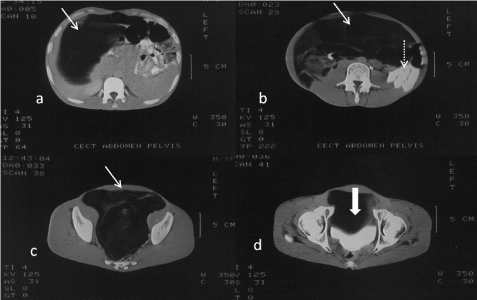

CECT abdomen was carried out to delineate the pathology better. A large lobulated, low attenuating, fat density mass was seen to occupy most of the abdominal cavity (Figure 2). It extended into the pelvis and extrinsic impression was seen on the anterior bladder wall. Septations were seen within the mass. Bowel loops were displaced to the left and also encased at places by this mass. Within this fat density mass, another well defined heterogeneously enhancing complex lesion, was seen in the region of the mesentery (Figure 3).

Figure 2. (a-d) CECT Abdomen. Scans show a huge low attenuating lipomatous mass occupying whole of the abdomen and pelvis (arrow). Bowel is seen displaced to one side (dotted arrow). Extrinsic impression on bladder is seen (thick arrow).